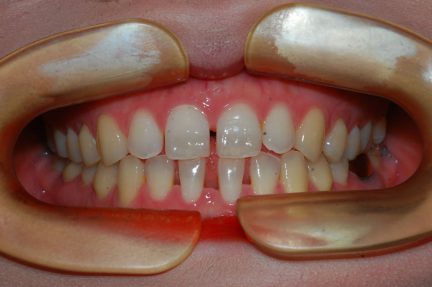

Expansion, nivellement de la courbe de Spee, réduction interproximale, fermeture de l'espace, pré-chirurgical

- Relation de classe I obtenue

- Guidage fonctionnel des canines des deux côtés

- Articulé antérieur corrigé

- Articulé postérieur corrigé

- Surplomb et recouvrement normaux obtenus

- Lignes médianes coïncidentes

- Alignement des deux arcades par dérotation

- Forme de l'arcade améliorée

- Cas où tous les objectifs du traitement ont été atteints

État final